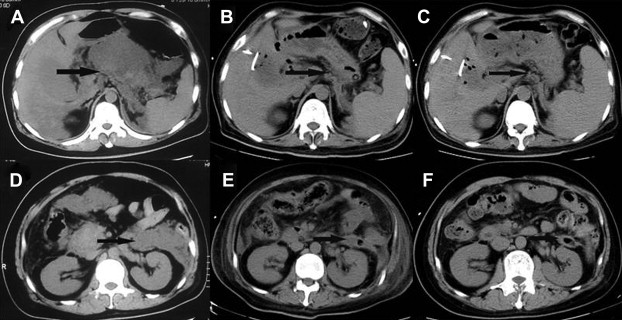

Two patients complicated by acute renal failure were hemodialyzed for 24–48 hours. Three patients showed acute respiratory distress syndrome (ARDS) and noninvasive mechanical ventilation was given to them. Two patients' conditions were improved after noninvasive mechanical ventilation was given. Laparoscopic debridement of necrotic tissue and drainage was conducted immediately, and endotracheal tube was used in the Intensive Care Unit (ICU) for a 78-year-old obese patient (body mass index = 36) with hypercholesterolemia and a history of hypertension and chronic heart failure, admitted to hospital because of 72 hours of left upper abdominal pain and high body temperature (39.8°C). His condition deteriorated sharply 3 days after admission, and ARDS was found. This patient died 2 days after surgery due to acute heart failure and ARDS. The other patients were cured or discharged with drainage tube (Fig. 2).

Laparoscopic retroperitoneal debridement and gallbladder puncture and drainage ...

Figure 2.

Laparoscopic retroperitoneal debridement and gallbladder puncture and drainage treatment for a 37-year-old male patient. (A) Lesser sac abscess prior to surgery. (B) Lesser sac abscess was significantly improved 20 days after surgery. (C) Lesser sac had no significant effusion 160 days after surgery. (D) Perinephric abscess prior to surgery. (E) Perinephric abscess was markedly improved 20 days after surgery. (F) No perirenal effusion was found 160 days after surgery. Arrow shows position of retroperitoneal infection.